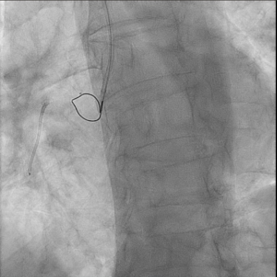

In view of this complication and the clinical instability of the patient, extraction of the device with a coronary snare was attempted but was unsuccessful (Figure 3). The access route was then changed to the femoral artery using an Amplatz left 6F catheter, and a Sion guidewire was advanced to the distal segment of the right coronary artery with the support of a 135-cm FineCross microcatheter (Terumo). This was followed by dilatation using a Sapphire II PRO balloon (OrbusNeich) (Figure 4) with catheter extension and anchoring of the balloon until 2 new everolimus-eluting stents (2.5 x 40 mm and 3.0 x 15 mm) could be advanced (Figure 5). Upon post-dilation of the noncompliant balloon, the previous stent and ballon were successfully crushed, obtaining a good final angiographic result (Figure 6). The procedure was completed with intracoronary optical coherence tomography, which confirmed adequate stent expansion and apposition, as well as the crushing of both the stent and the previous balloon (Figures 7-11).